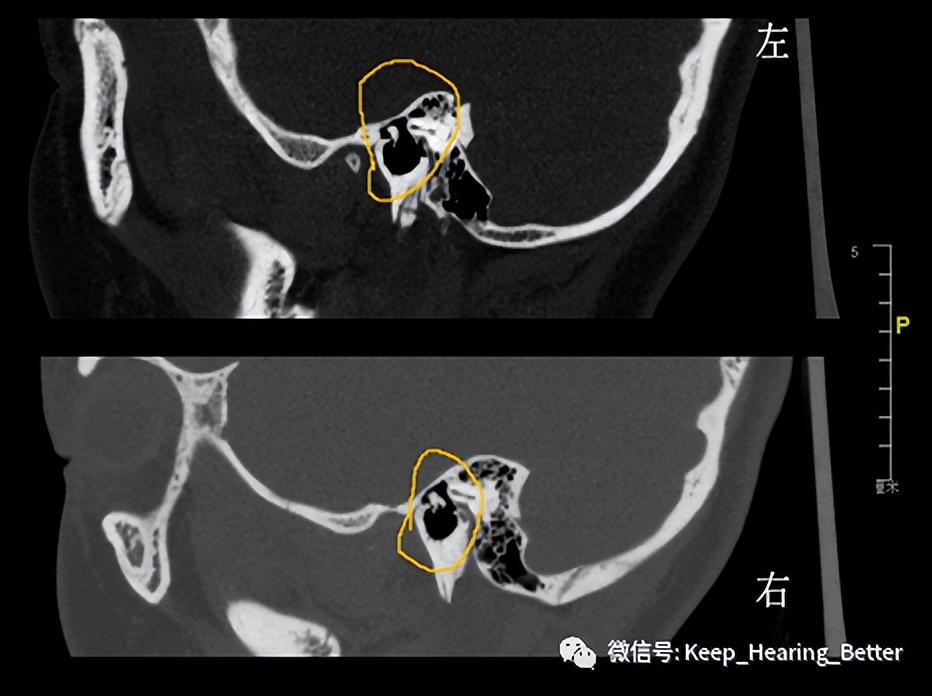

颞骨CT冠状位,左右对比可见右侧砧骨长突与镫骨相连,左侧砧骨长突缺如

颞骨CT矢状位可见右侧锤砧关节显示正常,左侧仅有锤骨头显示,未见砧骨体